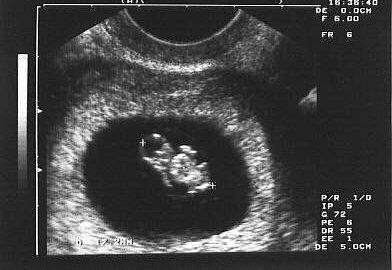

Early Sonography

Before 10 weeks

- It tells you whether it is single or multiple pregnancies (Twins / Triplets).

- If you have observed any spotting or bleeding.

For this, Sonography is done vaginally (internal examination).